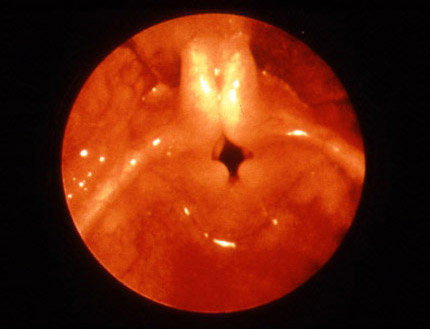

Endoscopic view showing collapse of the epiglottis.